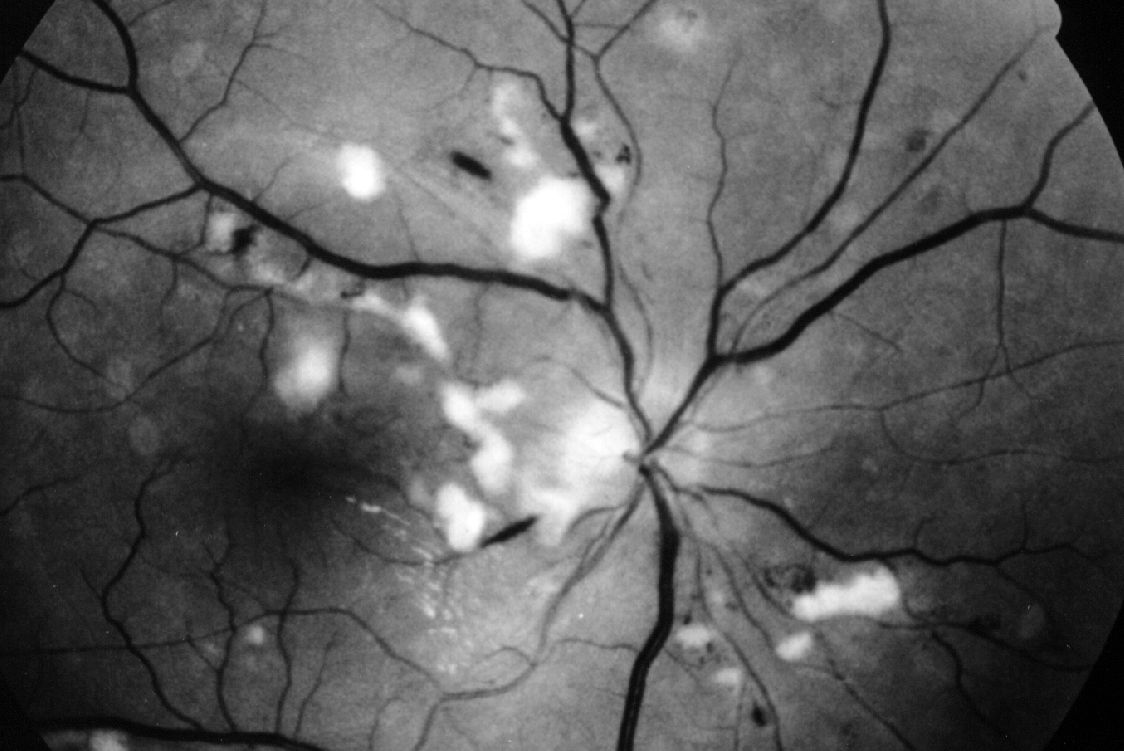

rétinopathie hypertensive